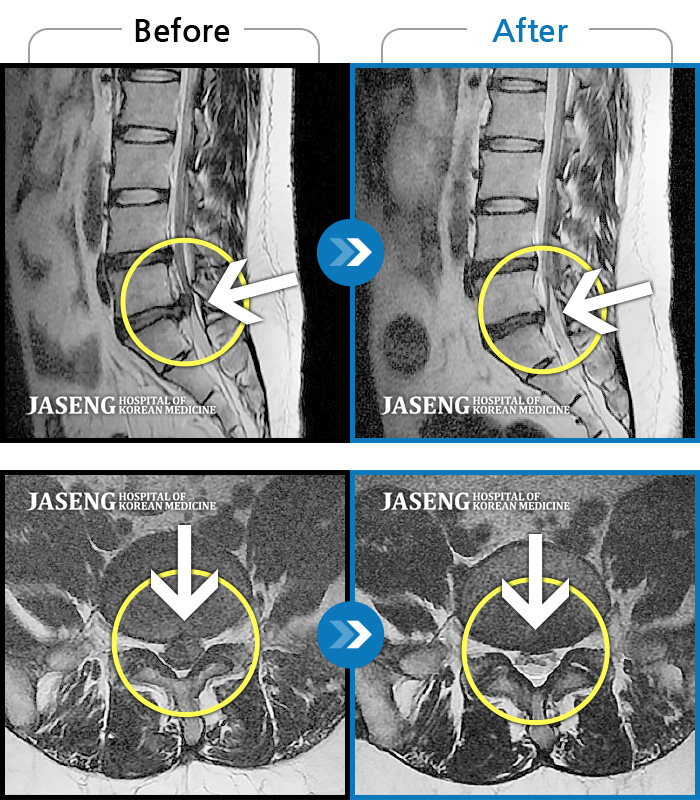

허리디스크

일산 · 배영현 원장

처음 내원 시 허리와 좌측 골반이 많이 아프고, 좌측 다리로 저림과 감각 저하가 있어서 보행이 원활하지 못했으며, 야간통으로 잠도 못 자고 통증 심하여 정상적인 활동이 힘든 상태셨습니다.

촬영시기

2023.09.16 ~ 2024.09.24

2024.10.04